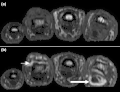

T1 weighted axial MRIs of the fingers in PsA. (a) Pre- and (b) post-contrast showing dactylitis due to flexor tenosynovitis at the second finger with enhancement and thickening of the tendon sheath (large arrow), and synovitis at proximal interphalangeal joint (small arrow). -